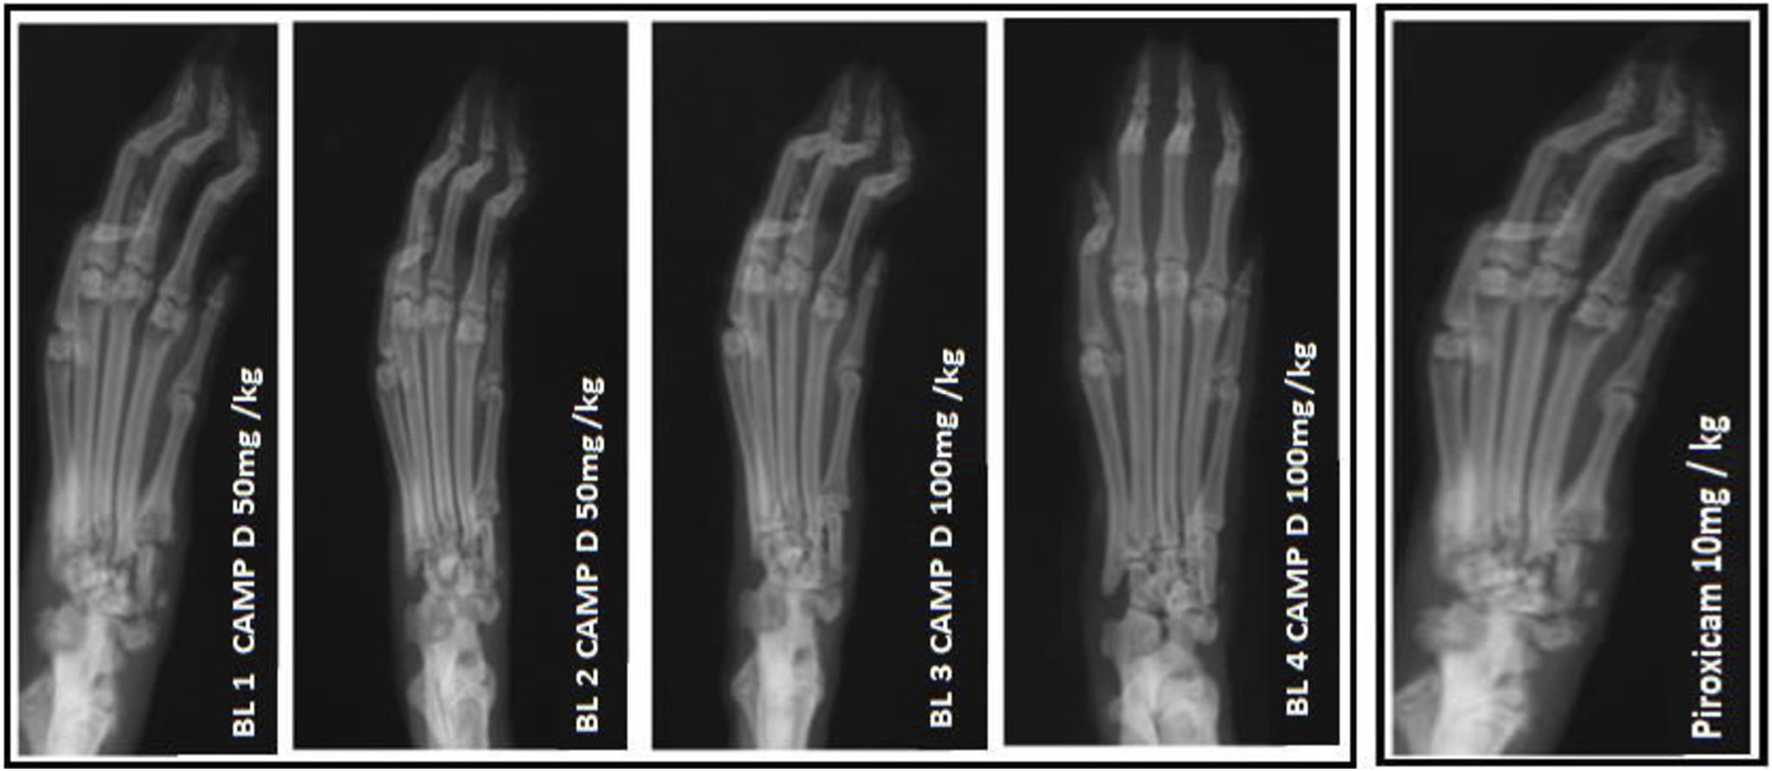

In the FCA-induced Arthritic rat model, CED (Compound E Derivative) was administered and compared to the illness group. The results revealed significant findings (***p < 0.001), as depicted in Figure 2. Over 28 days, CED exhibited a gradual increase in paw edema levels. At day 28, when compared to the positive control group (1.52 ± 0.05), both the CED derivative at 50 mg/kg (0.69 ± 0.02) and 100 mg/kg (0.79 ± 0.017), as well as piroxicam (0.74 ± 0.003), demonstrated inhibitory effects on paw edema. The paw edema progression was assessed, and the results were analyzed by the end of the 22nd day. On the 28th day, the difference in paw edema inhibition between the CFA-induced and positive control groups was 1.52 ± 0.05. X-rays of rats’ lower limbs were taken using a Siemens X-ray machine to assess joint variations. The analysis was based on joint space and swollen soft tissue. Figure 3 illustrates anteroposterior (AP) view of X-rays of rat paws on the 21st and 28th days for both the normal and arthritic rat groups. X-rays were also utilized to evaluate arthritis using piroxicam 10 mg/kg. X-ray photographs of the normal rat paw showed the presence of 8 Joint Spaces, 8 Soft tissues, and 3 metatarsal bones. On the other hand, CFA rats from the vehicle treatment group exhibited several deformities, including significant paw edema, osteophyte development, decreased joint spacing, and bone degradation.

FIGURE 3

X-ray photographs of the normal rat paw illustrating the AP view of X-rays.